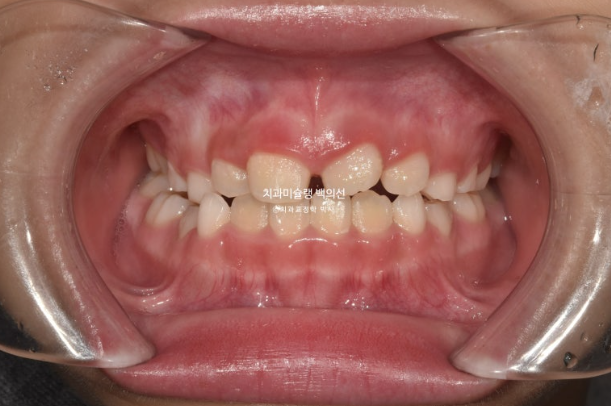

2022.10

하지만 여전히 어금니 반대교합이 남아있습니다.

유치 송곳니도 여전히 거꾸로 물려 교합간섭이 남아있습니다.

어금니 반대교합은 상악 악궁이 좁아서 생기는 문제입니다.

즉 악궁확장이 필요하고 인비절라인 퍼스트로 악궁확장을 동반하여 MA (mandible advance, 하악전진기능) 기능을 이용한 비대칭 치료가 필요합니다.